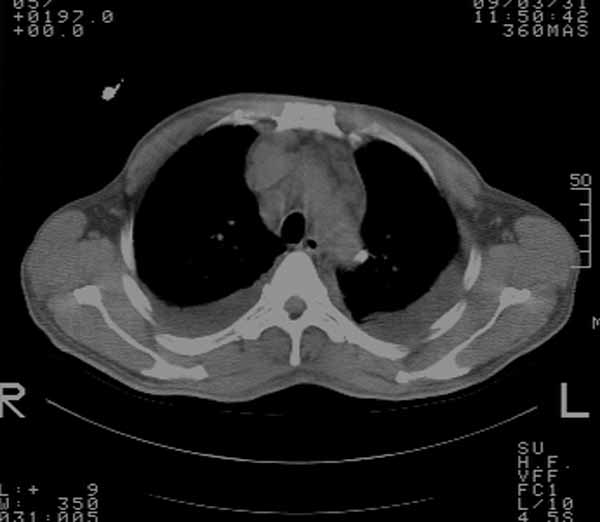

以下是引用余辉在2009-3-31 18:43:00的发言:[br]肺水肿,双侧心腔积液,心包积液,心影增大,疑似心衰

以下是引用wangyong1977在2009-3-31 20:46:00的发言:[br]肺水肿,双侧胸腔积液,心包积液,心影增大,疑似心衰 [br]

以下是引用宇宙ct在2009-3-31 18:57:00的发言:[br]肺水肿,双侧心腔积液,心包积液,心影增大,疑似心衰 [br] [br]